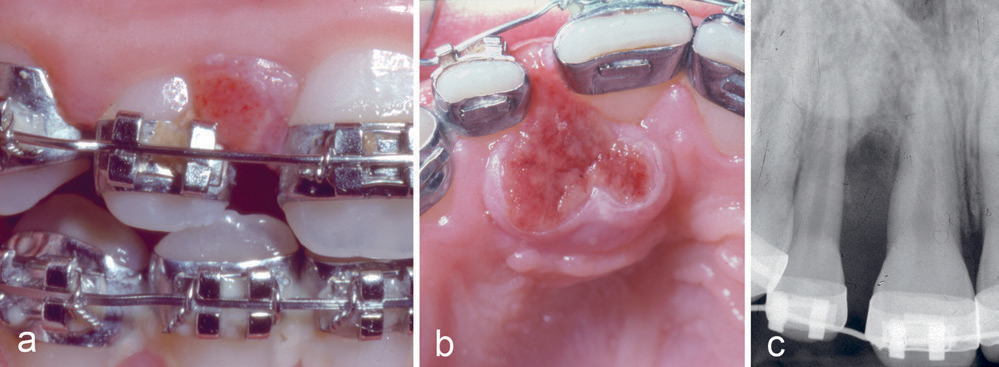

Kasus 1

En elleve år gammel pike var henvist fra kjeveortoped for fjerning av tumor mellom tennene 11 og 12. Det fremgikk av anamnesen at pasienten hadde hatt tannreguleringsapparatur i to år og at hun hadde dårlig munnhygiene. Det var fjernet en lesjon i samme region hos tannlege seks måneder tidligere, et residiv ble fjernet tre måneder senere hos lege ved en kirurgisk poliklinikk. Nå var det et nytt residiv. Det var mobilitet av tennene 11 og 12 og en rød-brun lesjon (figur 1a, b), som strakte seg fra marginalkanten til 5 mm fra apex på 11 og 12 (figur 1c). Lesjonen ble skrapt nøye ut, og det ble suturert en pakning over det blottlagte benet. Diagnosen PKCG ble bekreftet histologisk.

Figur 1. Kasus 1. PKCG mellom tann 11 og 12 (a, b) med tap av marginalt ben (c) hos en elleve år gammel pike.